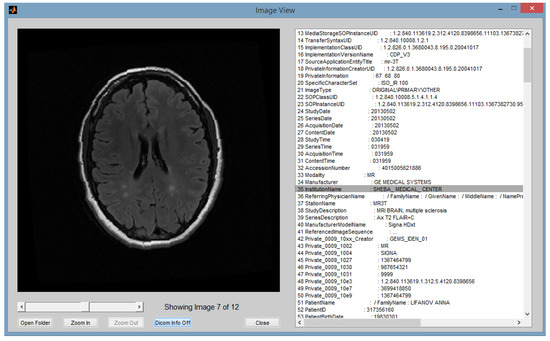

2.1. File Type Selection